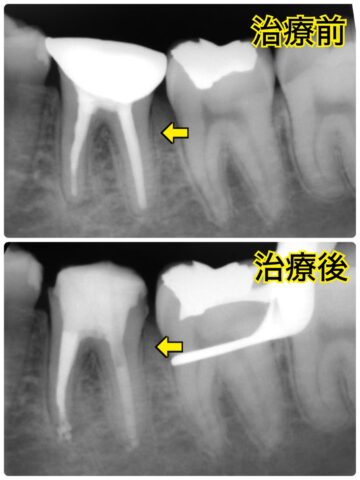

もう1本神経が無い歯も再治療したいとご希望されたのでその歯も感染根管治療を行いました!

ですが、インビザライン中に

感染根管治療を行った左の奥歯(2本目の感染根管治療をした歯)にトラブルが起きてしまいました…

根に大きな穴があいてしまいました…

恐らく今まで大きな負担がかかっていたのでそれが原因で元々ヒビが入っており

根の歯質がそれが耐えきれず欠けてしまったと考えられます😭

その歯は残念ながら保存はできず抜歯になってしまいましたが、インプラント治療を行いました。